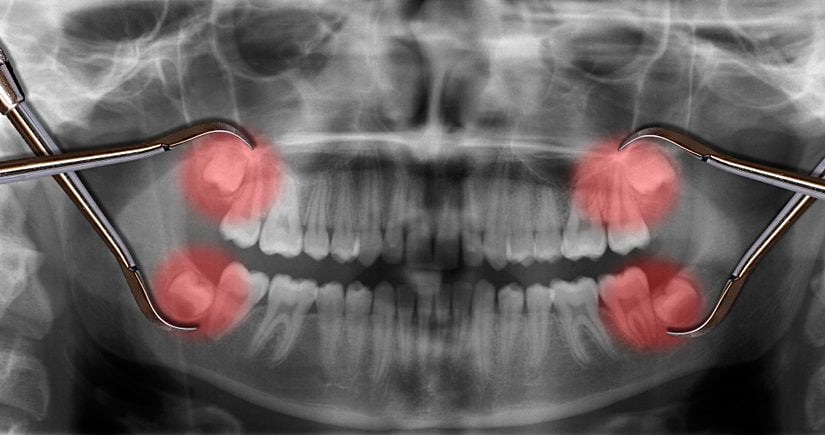

Yirmi yaş dişlerinin sıklıkla gömülü kalırlar, çıktıkları zaman doğru şekilde çıkmazlar ve diğer dişlere sürtünerek onların yapısını bozabilirler. Bu nedenle de ağrı ve enfeksiyona neden oldukları bilinmektedir. Bunun haricinde ise hiçbir işlevleri bulunmamaktadır. Dolayısıyla ağrıya neden oldukları zaman, diş hekimleri tarafından çekilerek hasta rahatlatılabilmektedir. 20 yaş dişleri çekilen kişilerin ağız fonksiyonlarında hiçbir azalma olmamaktadır. Aşağıda bu dişleri görmektesiniz:

Uzun yıllar insanlar bu dişlerin en başından neden var olduğunu anlayamamış ve bir çeşit "lanet" olarak görmüşlerdir; zira 20 yaş dişlerinin çıkmaya başlamasından çekilene kadar verdiği acıyı, bu dişleri sorunlu olarak çıkan kişiler gayet iyi bilirler. Ancak evrimsel biyolojinin gelişimiyle birlikte öncelikle insan evrimine ışık tutulmuş, daha sonra da bu tip körelmiş organların varlığı açıklanmıştır. 20 yaş dişleri de, insanda görülen 40'tan fazla körelmiş organ ve yapıdan sadece birisidir. Aşağıda, bu körelmiş yapıların ne şekilde hatalı oluşabileceklerine örnekler görülmektedir: